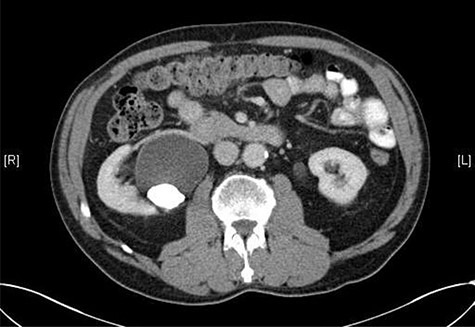

A 72-year-old male with a history of bleeding per rectum underwent an outpatient colonoscopy, which demonstrated a large villous tumour occupying the caecal pole. A staging CT thorax, abdomen and pelvis was subsequently performed confirming the presence of tumour with liver metastases and an incidental 33 × 21 mm calculus in the right renal pelvis with associated hydronephrosis (Fig. 1).

CT scan showing a staghorn calculus in the right renal pelvis with associated hydronephrosis.